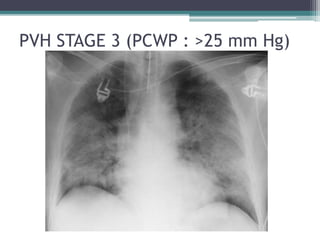

• ALVEOLAR EDEMA

• Cotton wool appearance

• “Bat wing” appearance

• PCWP : >25 mmHg

STAGE 3

PVH STAGE 3 (PCWP : >25 mm Hg)

PVH STAGE 3(PCWP : >25 mm Hg)